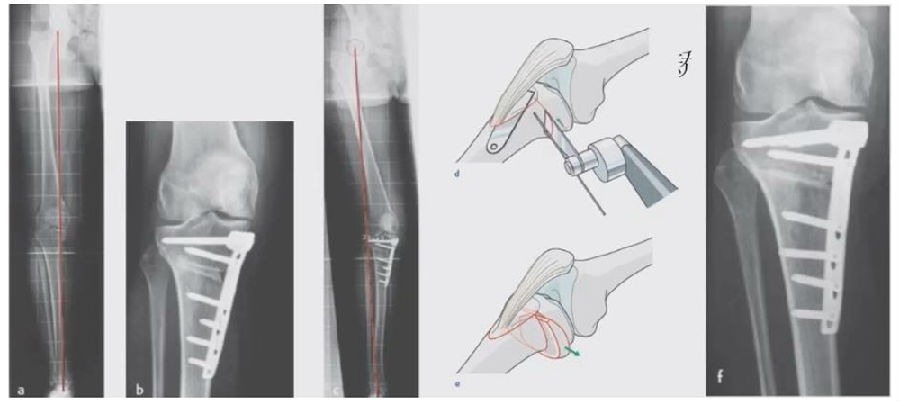

2、处理

(1)如果在手术台上,或是刚做完手术就发现矫正不良问题,此时比较简单。需要先跟患者进行沟通,在手术中直接将远端4颗螺钉卸下来,调整好力线后重新打入即可。但是注意要把远端单皮质螺钉换成双皮质螺钉。

(2)如果患者已经达到初始愈合,此时如果出现过度外翻,需要在内侧重新做内侧闭合楔。

(3)如果做完手术时间较长,出现过度矫正或矫正不足时,需要重新做力线分析,看一看力线在哪个方向可以再进行调整。胫骨侧有调整余地,就在胫骨侧进行调整;股骨侧需要调整,就在股骨侧进行调整。

3、总结

矫正不良与肢体位置、MCL浅层松解不够、力线验证及拉力螺钉加压过度有关。

要注意术前放置肢体于中立;MCL浅层彻底松解;外翻应力下验证力线;合理的拉力螺钉加压;及时处理发生的矫正不良。